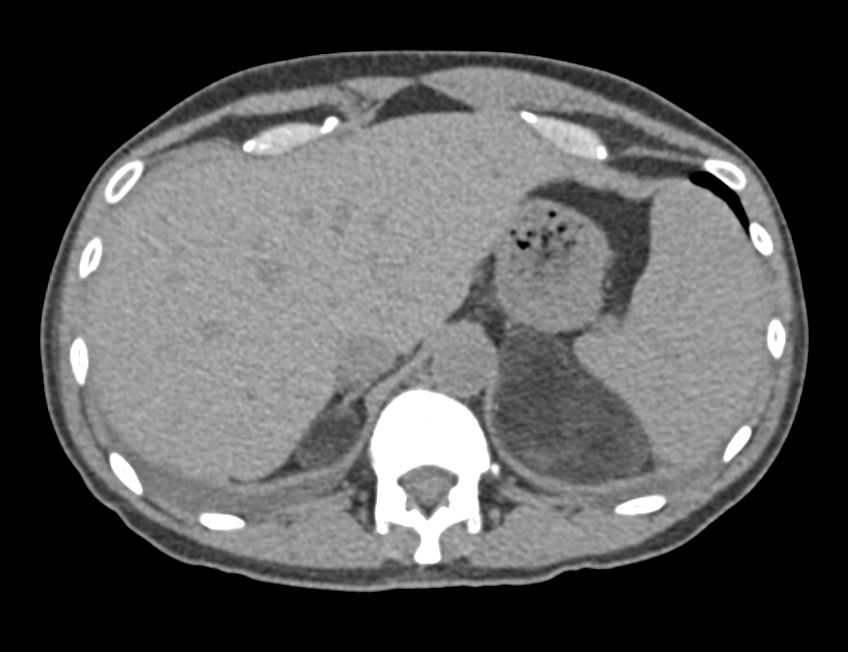

Carcinoma of the Head of the Pancreas